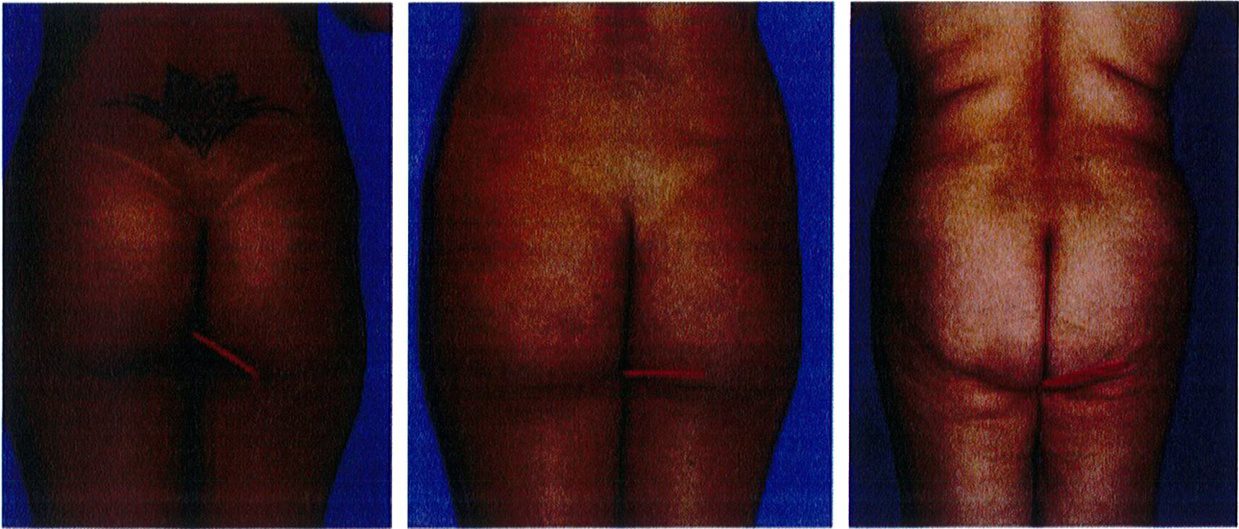

Để mô tả khối cơ mông trong mối tương quan giữa nếp lằn mông và đùi, hãy lấy đường liên mông làm trung tâm. Đầu trên của đường liên mông có thể xác định một cách rõ ràng; tuy nhiên, đầu dưới thì không dễ dàng như vậy. Điểm dưới cùng này là nơi mà hai bên mông tách ra từ đường giữa. Nếu lý tưởng thì điểm dưới này phải nằm ở 2/3 dưới hoặc ¾ dưới của chiều cao khối cơ (Hình 22). Hai mông tiếp tục tách về hai phía cho tới khi chúng gặp ‘khớp nối’ vùng đùi trong. Tại vị trí này, nếp lằn mông hợp với đường liên mông góc 45°.

Hình. 22. Nếp lằn mông (đường màu đỏ) có thể tồn tại ở ba dạng là đường dốc xuống (lý tưởng), đường ngang, và đường dốc lên.

thừa ở nếp lằn mông (hình 23). Nếu lý tưởng, nếp lằn mông nên kết thúc ở giữa mông đó hoặc có thể ra ngoài một đoạn ngắn.

Khối cơ mông trong mối tương quan của mặt dưới ngoài đùi và giữa ngoài hông

Nếu lý tưởng, tương quan giữa nếp lằn mông hai bên và vùng đùi trong tạo ra 1 cấu trúc tưởng tượng hình thoi (chính là vùng 6 trong 8 đơn vị thẩm mỹ) (Hình 22). Nếu nếp lằn mông nằm ngang thì gần như cấu trúc hình thoi kia sẽ chuyển dạng thành 1 đường thẳng, điều này làm giảm tính thẩm mỹ của vùng mông. Khi mông bị sa, nếp lằn mông lúc này lại tạo với mặt trong đùi một góc âm (đối nghịch với vùng mông lý tưởng), làm ảnh hưởng rất xấu tới tính thẩm mỹ. Để đánh giá vùng mông, độ nghiêng của nếp lằn mông được xác định là một đường thẳng dốc xuống, đường ngang hoặc dốc lên và góc tạo bởi nó và đường liên mông là góc nghiêng (tính bằng độ).

Hai điểm bám cuối cùng của cơ mông phải được đánh giá là ‘khớp nối’ mặt dưới ngoài mông với đùi và ‘khớp nối’ vùng giữa ngoài mông với mặt ngoài đùi. Nếu lý tưởng (Hình 24 và 25), bờ các cơ vùng mông có thể không xác định được vì chúng nối liên tục với khu- ng, thống nhất thành 1 khối. Tuy nhiên, ở một số bệnh nhân, phần bờ ngoài của khối cơ lại xác định được rõ ràng, tạo ra một đường lõm không thẩm mỹ.

Để cải thiện tình thẩm mỹ vùng này, nên xác định kiểu hình nếp lắn mông trước khi đưa ra phương án điều trị. Nếu nếp lằn mông nằm ngang (Hình 22), có thể chỉ định hút mỡ vùng đùi trong và nếp lằn mông. Nếu nếp lằn mong là một đường hướng lên trên (hình 22c) thì nên thực hiện hút mỡ cả đùi trong cũng như nếp lằn mông, đồng thời xem xét cắt bỏ vùng da

Các vùng chuyển tiếp này nên được đánh giá và phân loại là chuyển tiếp liên tục (không thấy mép cơ), vừa phải (đường ranh giới chúng tạo ra không rõ nét), và không liên tục (đường ranh giới rõ nét) (xem hình 24 và 25). Khi sự phân tách này ngày một rõ, nên xem xét để tiêm lipofiller giúp đường chuyển tiếp trở nên liên tục.